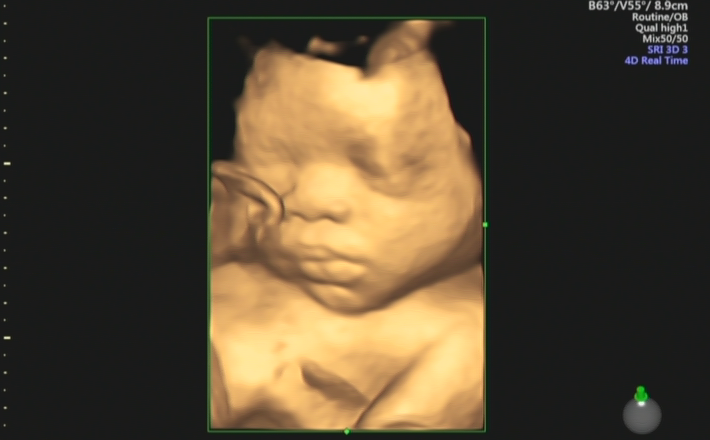

孕中期四维大排畸

B超大排畸是孕中期的关键产检,可以通过四维彩超、系统超声、心脏彩超等项目排除大部分胎儿发育畸形。

检查时间:单胎时间是在22-28周为佳;双胎时间在20-24周为佳。

主要筛查缺陷:主要是观察胎儿在宫内的情况,通过检查五官、四肢、骨骼、心脏、肾脏各器官的症状表现,判断胎儿是否健康,是否存在发育畸形的问题。

我院还引进美GE系列超声仪器,细致的多切面成像分析胎儿的解剖结构及发育状况,能够提供更多、更精准的图像数据,可以更加清晰、完整地记录胎儿宫内的高清动态,满足从早孕期到孕晚期的全程早期检查和诊断。